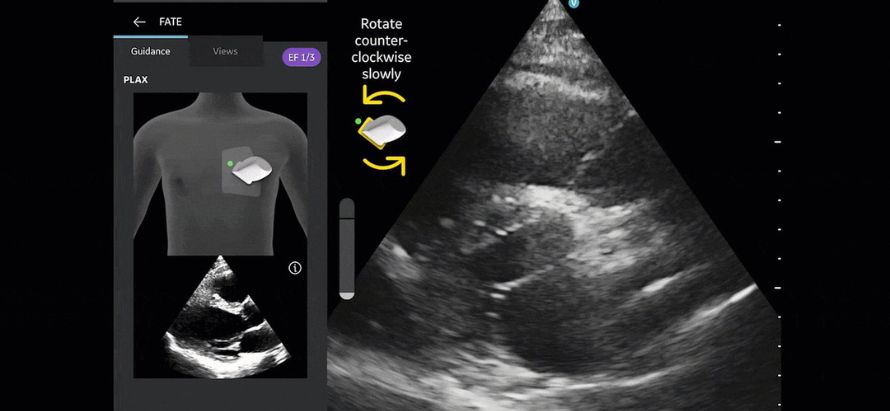

T-Mode Heart works by applying advanced AI models to live ultrasound images in real time. As the clinician scans the patient’s heart, the system automatically recognizes and labels essential anatomical structures including the left ventricle, right ventricle, atria, valves, pericardium, and major vessels while providing visual guidance on probe positioning and image optimization. The tool also displays standard cardiac measurements (ejection fraction estimation, chamber dimensions, and pericardial effusion assessment) and offers educational overlays explaining normal versus abnormal findings, helping users build competence rapidly.

The solution is fully integrated into Clarius’s wireless handheld ultrasound scanners, requiring no additional hardware or complex setup. It supports multiple cardiac windows (parasternal long-axis, short-axis, apical four-chamber, and subcostal views) and is designed to work in both emergency and routine primary care settings. Early feedback from pilot users indicates that T-Mode Heart significantly reduces the time required to acquire diagnostic-quality cardiac images and improves diagnostic confidence among non-specialist physicians.